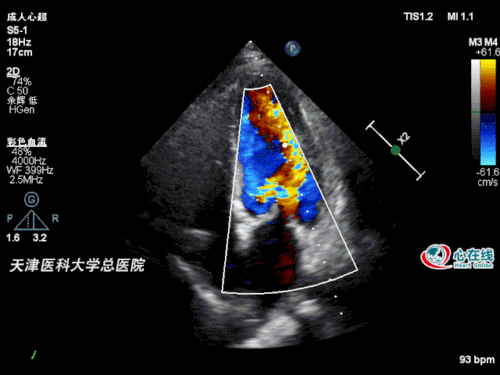

图2. 二尖瓣m型超声示前叶,后叶开放幅度减低,开放间距减小.

二尖瓣狭窄超声心动图